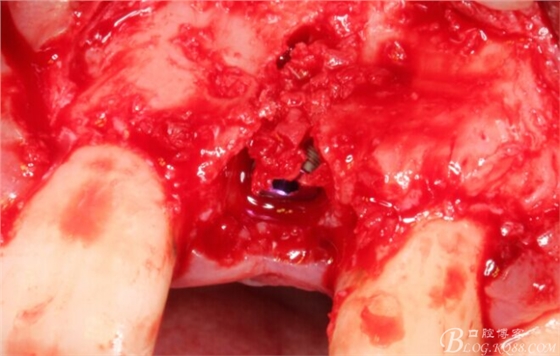

擴(kuò)孔。

骨擠壓。

植入植體。